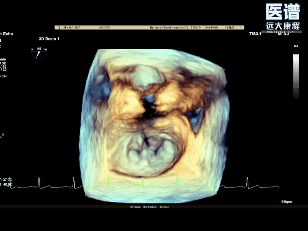

释放后3D评估(组织桥稳定)

释放后3D评估(反流少量)

术后,多位现场观摩的国际专家点评指出,本例患者为重度DMR,BMI仅17.5kg/㎡,同时叠加了高血压、房颤、肾功能不全等多重基础病,为手术的成功实施显著增加了难度。术中,得益于王建安院士及刘先宝教授清晰的策略及精准的操作,再配合手术团队自主创新研发的DragonFly经导管瓣膜修复系统,在3D影像引导下精准锁定病变区域,完成修复操作,最终实现了‘效果与安全并重’的理想治疗效果,为全球TEER手术的高效、安全开展打造了可借鉴、可复制的中国样板。”

术中完成房间隔穿刺后,将可操控导引导管(SGC)及二尖瓣夹输送系统成功送入左心房。随后将瓣膜夹调整至二尖瓣上并逐步移至病变区域,经轴向调整后,夹合器于A1/P1交界区顺利捕获瓣叶并完成首次夹合,此时超声提示存在少量反流;为达到更优的治疗效果,王建安院士及刘先宝教授决定微调位置,打开夹合器调整轴向后,重新捕获瓣叶以夹合瓣叶并成功释放,最终有效解决了反流及脱垂问题。释放后食道超声评估仅存在少量反流,平均跨瓣压3mmHg,圆满完成手术。